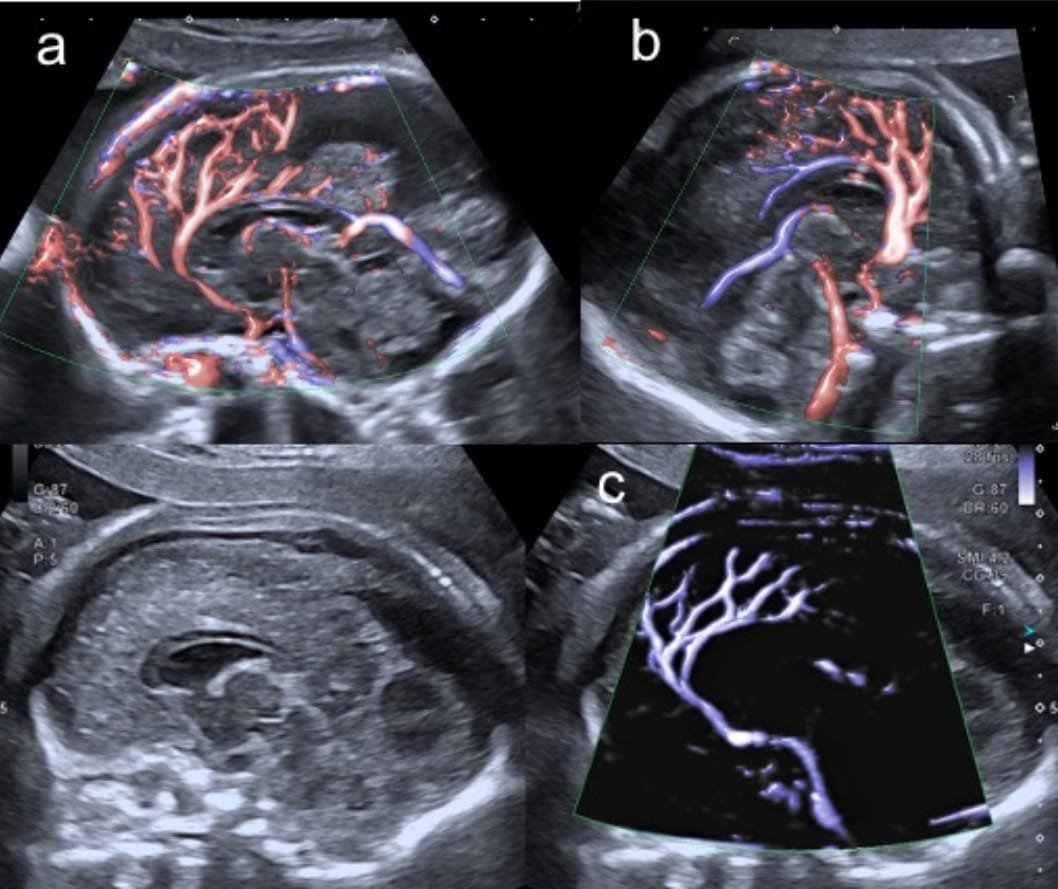

Doppler Scan

The Doppler scan is a specialized test used to measure blood flow in the placenta, umbilical cord, and fetal organs. It plays a vital role in monitoring high-risk pregnancies by ensuring that the baby is receiving enough oxygen and nutrients. This scan is often recommended in the third trimester or when growth concerns are present. Our expert team at Tiny Hearts uses this tool to closely track fetal well-being and intervene when needed.

Fetal Neuro Sonogram

This advanced ultrasound focuses on the detailed imaging of the baby’s brain and central nervous system. A fetal neuro sonogram is especially important in pregnancies with abnormal early scans, genetic risk factors, or maternal infections. It helps in detecting neurological conditions at an early stage. At Tiny Hearts, we use cutting-edge neuroimaging to provide clarity and confidence for your baby’s neurological health.